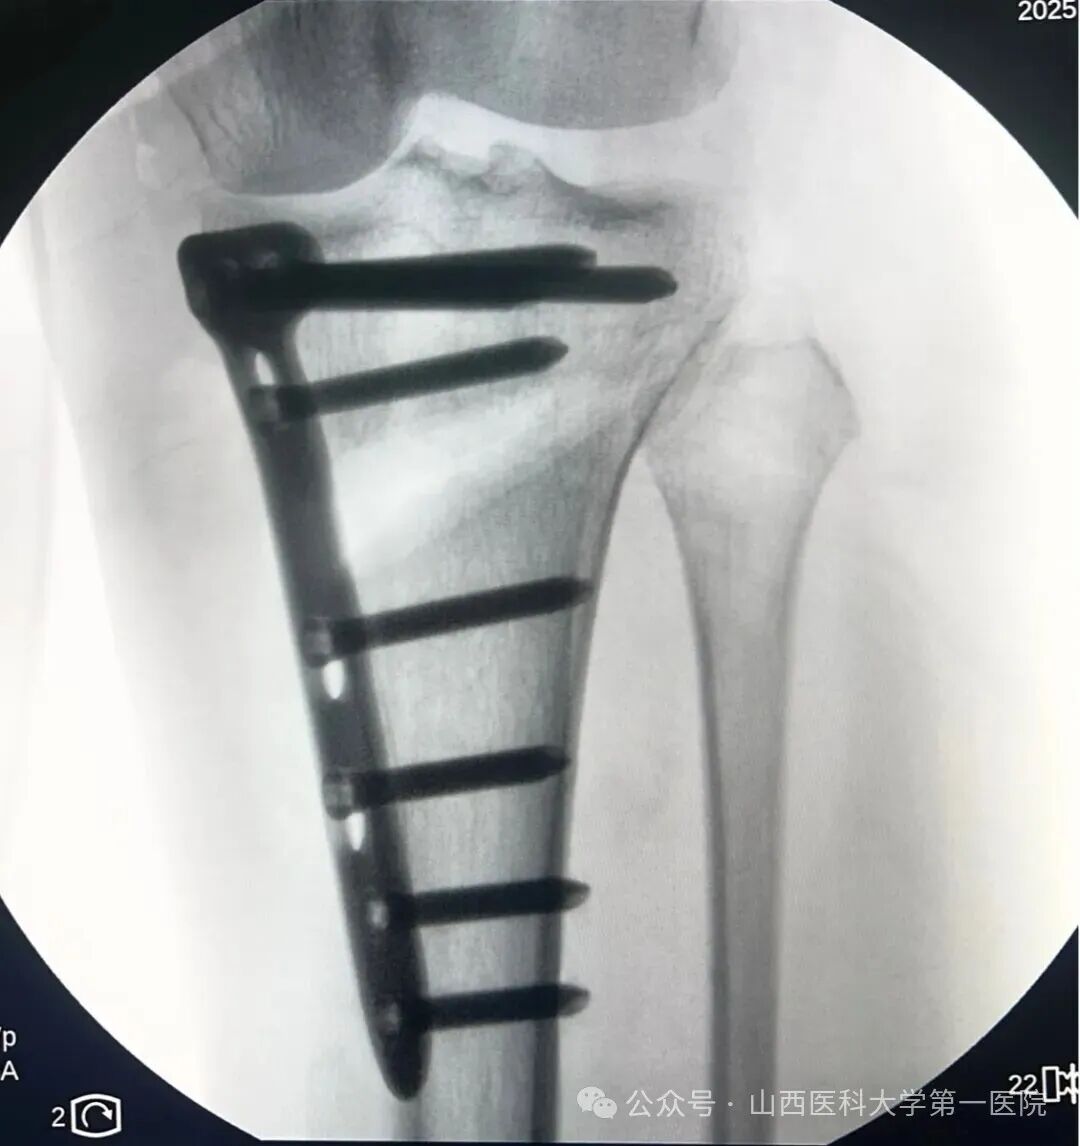

放置钢板后行X线确认位置满意